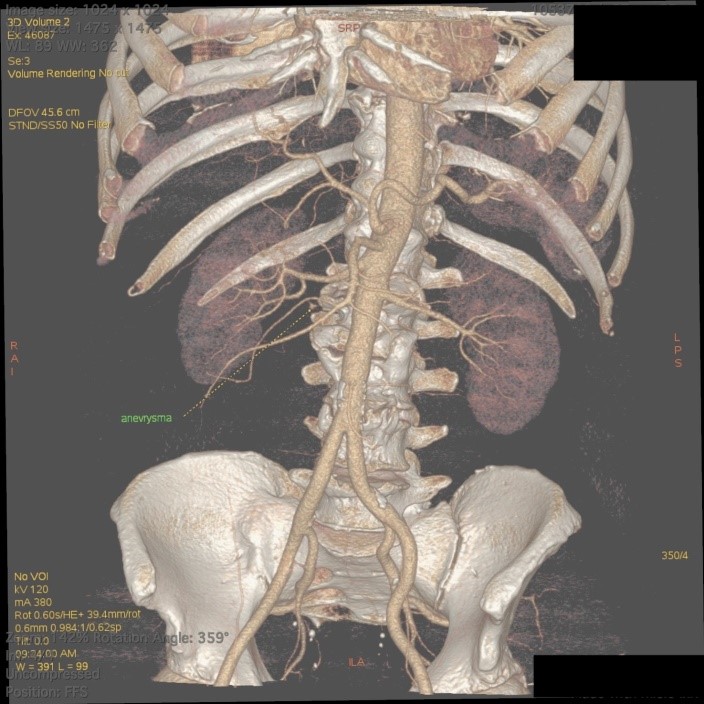

На амбулаторном этапе обратился в «Адамант Медицинская Клиника», где на протяжении последних лет проходит диспансерное наблюдение. Учитывая, что источник кровотечения не был установлен, было принято решение выполнить ангио-МСКТ брюшного отдела аорты и ее ветвей, что и выполнено 25.08.2021 г., по результатам которого выявлена аневризма нижней панкреатодуоденальной артерии. С целью уточнения диагноза рекомендовано выполнение ангиографии аорты и артерий брюшной полости, с последующим решением вопроса о необходимости оперативного лечения (эмболизации) (рис. 1, 2).

Рис. 2. 3D-реконструкция. МСКТ-ангиография брюшной аорты и ее ветвей.

Fig 2. 3D-reconstruction. MSCT angiography of the abdominal aorta and its branches.